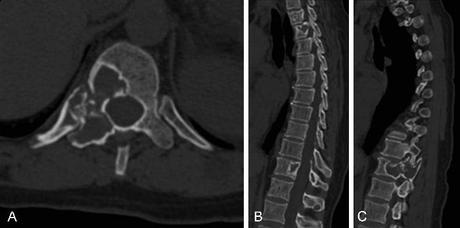

Esta técnica quirúrgica

inicia con una exposición de toda la columna dorsal, sacra y parte de la pelvis

mediante la disección y elevación de los músculos y tendones que tiene adheridos.

La disección se basa en reconstrucciones

en 3D y biomodelos. Luego hay que liberar la médula espinal de la

deformidad, lo que se denomina desanclaje medular. Una vez conseguido, se

identifican las vértebras a extirpar, habitualmente un bloque malformativo

bastante complejo. Para ello, dr usan técnicas microquirúrgicas, resección ósea

mediante motores de alta velocidad y bisturís piezoeléctricos para ir

extirpando el hueso sin tracciones sobre las estructuras más delicadas.

Finalmente, el resto de vertebras se extrae y se utiliza como injerto de hueso.

En estos pacientes, muchos de ellos con parálisis de los miembros, los huesos

pélvicos son débiles por lo que se complementa la estabilización mediante

tornillos y barras colocados alrededor del hueso para darle más solidez. Esta

técnica se emplea en aquellos pacientes

con deformidades graves, con curvas de más de 90 grados y desequilibrio pélvico

extremo. Todo esto supone un grave compromiso de los órganos internos, sobre

todo el pulmonar, produciendo una restricción respiratoria importante y

reduciendo enormemente su esperanza de vida. Esta Técnica se realiza enla Unidad de Neurocirugía de los Hospitales

Universitarios Virgen Macarena y Virgen del Rocío, de Sevilla en España.